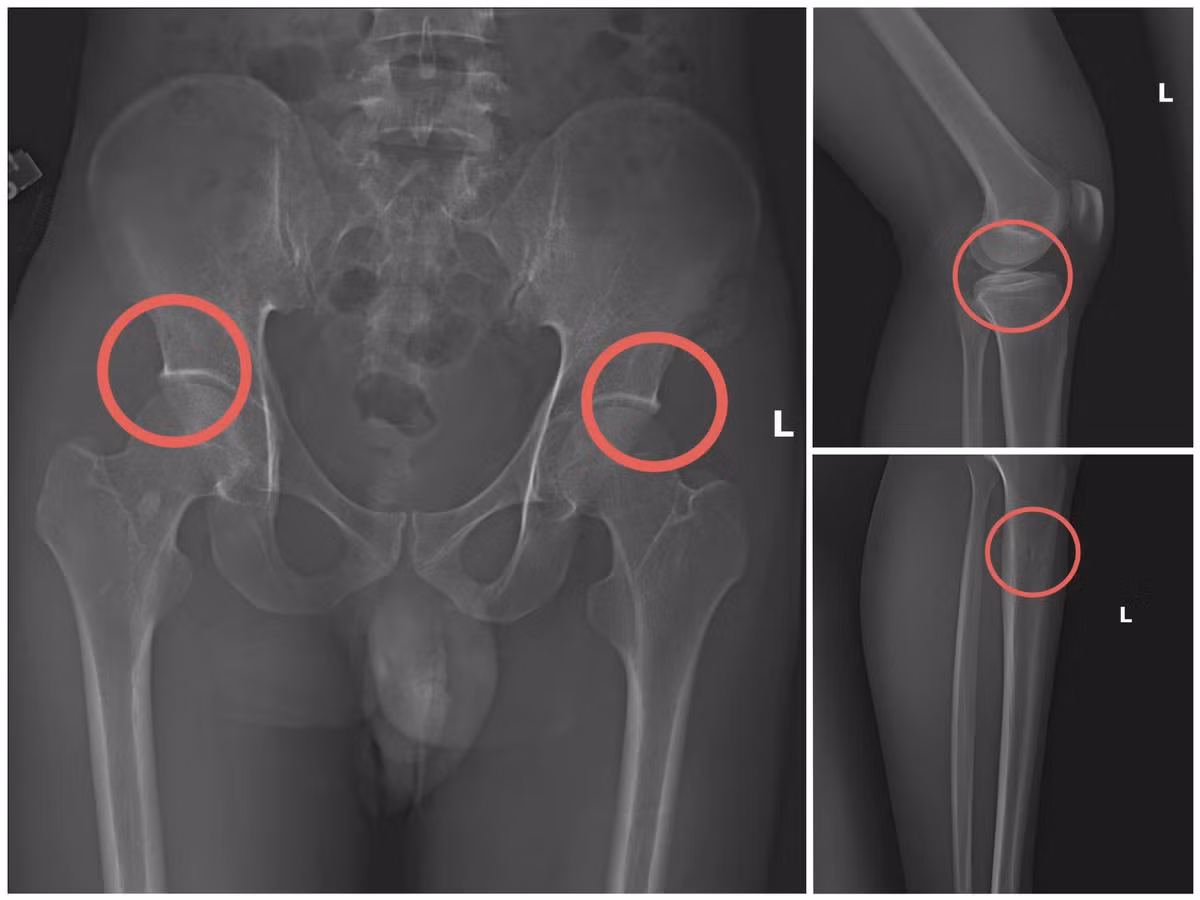

433.jpg

Bản phim chụp XQ một số tổn thương xương do đối tượng tạo ra

Châu từng có thời gian dài công tác trong ngành y, am hiểu sâu cấu tạo xương khớp và cơ chế chi trả bảo hiểm các thương tích gãy xương giá trị cao. Do đó, đối tượng này đã dựng lên một quy trình trục lợi bài bản, từ vận động mua bảo hiểm, tổ chức gây thương tích, hợp thức hóa hồ sơ bệnh án để chiếm đoạt tiền các công ty bảo hiểm.

Điều tra xác định, Châu trực tiếp tiêm thuốc mê rồi dùng kim tiêm, búa, đinh tác động vào xương người mua bảo hiểm, tạo nên các vết nứt, vỡ xương tương tự tai nạn thật. Khi tạo xong thương tích, Châu hướng dẫn các đối tượng dựng hiện trường giả như điện giật ngã, trượt chân ngã suối, nhằm hợp thức hóa bệnh án, hoàn thiện hồ sơ yêu cầu chi trả.